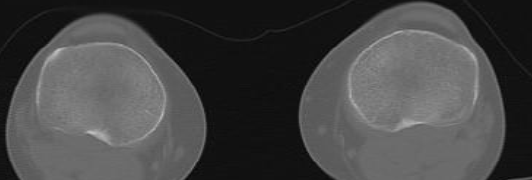

Coupes

A

Tête fémorale

C

Condyles (Arche romaine)